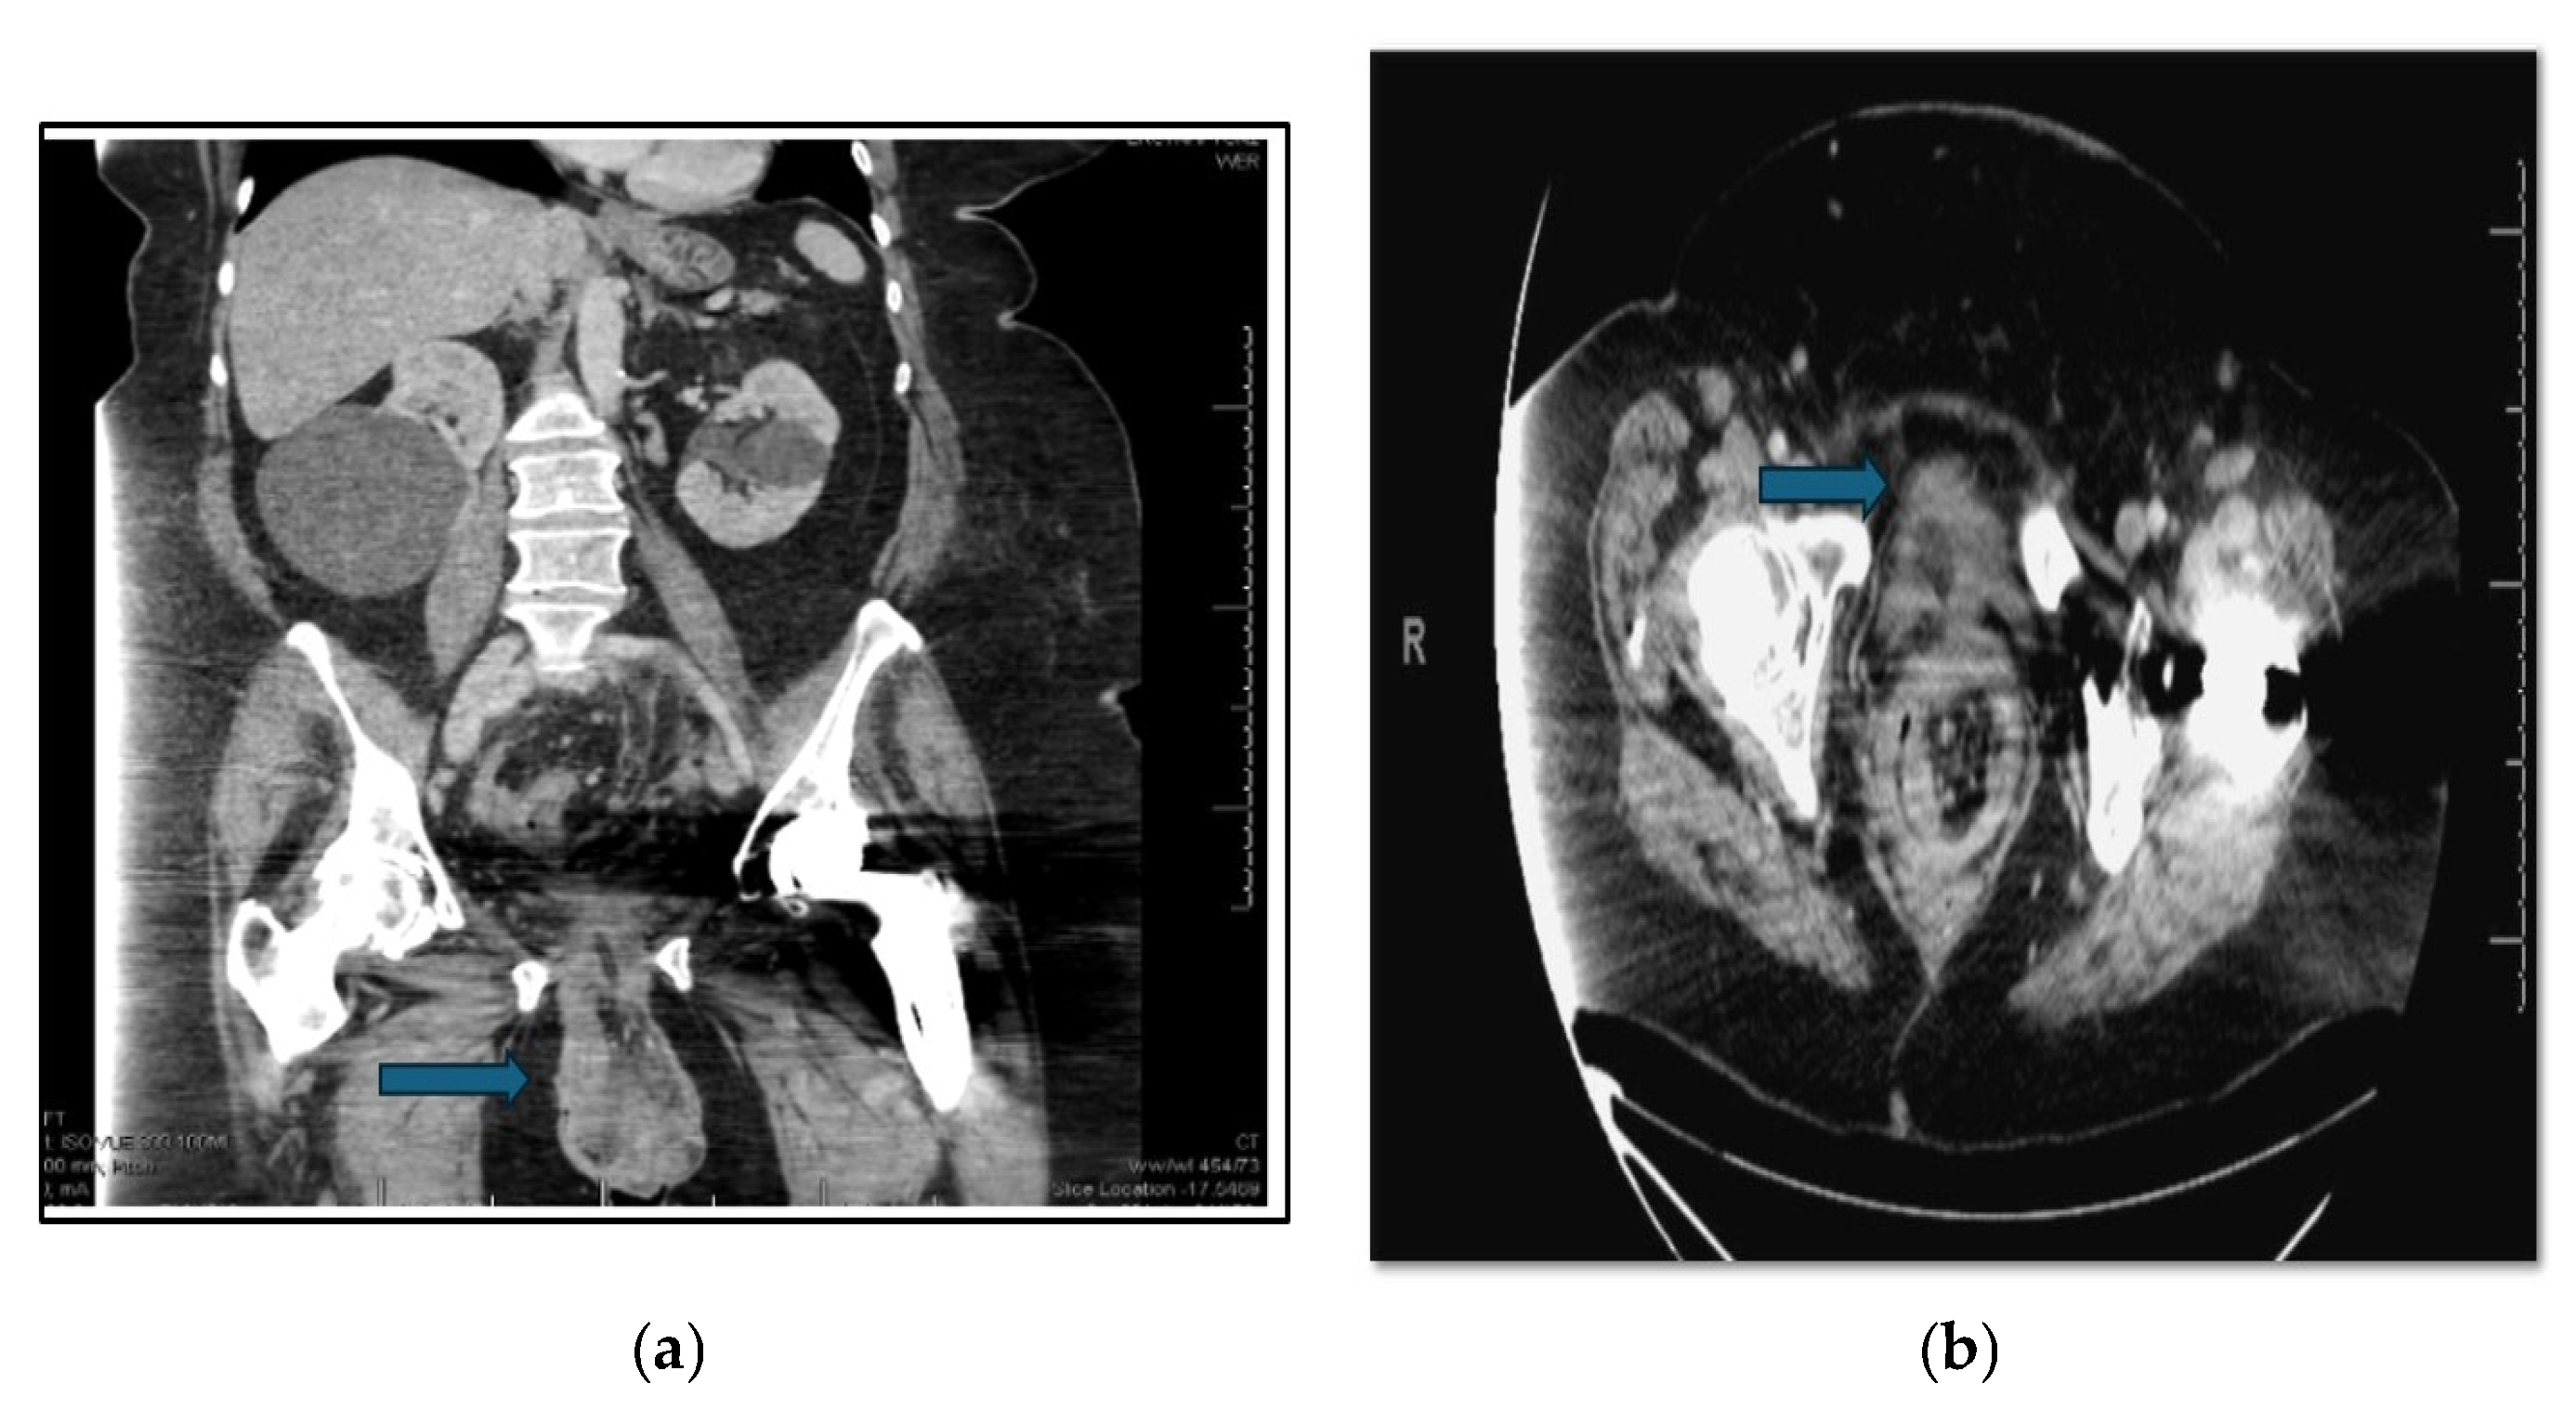

4. Laboratory and Imaging